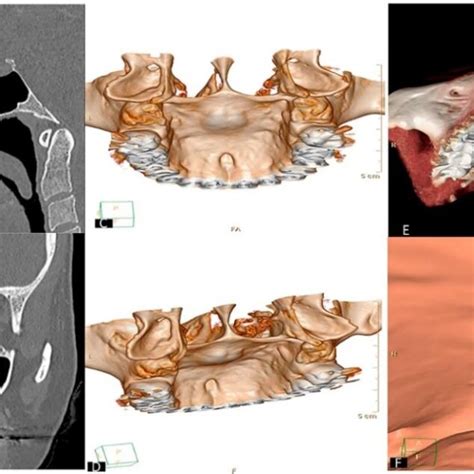

Ejemplo de torus mandibular, una posible causa de protuberancias óseas en la encía.

Los torus son protuberancias de hueso que pueden aparecer en los maxilares, con forma nodular, y generalmente sin ningún tipo de sintomatología acompañante. Pueden aparecer en el paladar o en la mandíbula.

Los torus palatinos se presentan en la línea media del paladar duro, en forma de protuberancias de un tamaño variable. Los torus mandibulares se presentan más frecuentemente en la cara lingual de la mandíbula, a la altura de los premolares, y suelen ser bilaterales.

También pueden formarse pequeñas protuberancias óseas múltiples, en la cara externa de los maxilares, preferentemente a la altura de los premolares, con formas nodulares, redondeadas u ovales. La encía que los recubre suele ser algo más pálida. Su tamaño suele ser pequeño, aunque a veces pueden crecer hasta interferir con la estética del paciente. Los torus no tienen ningún significado patológico, ni presentan sintomatología alguna.